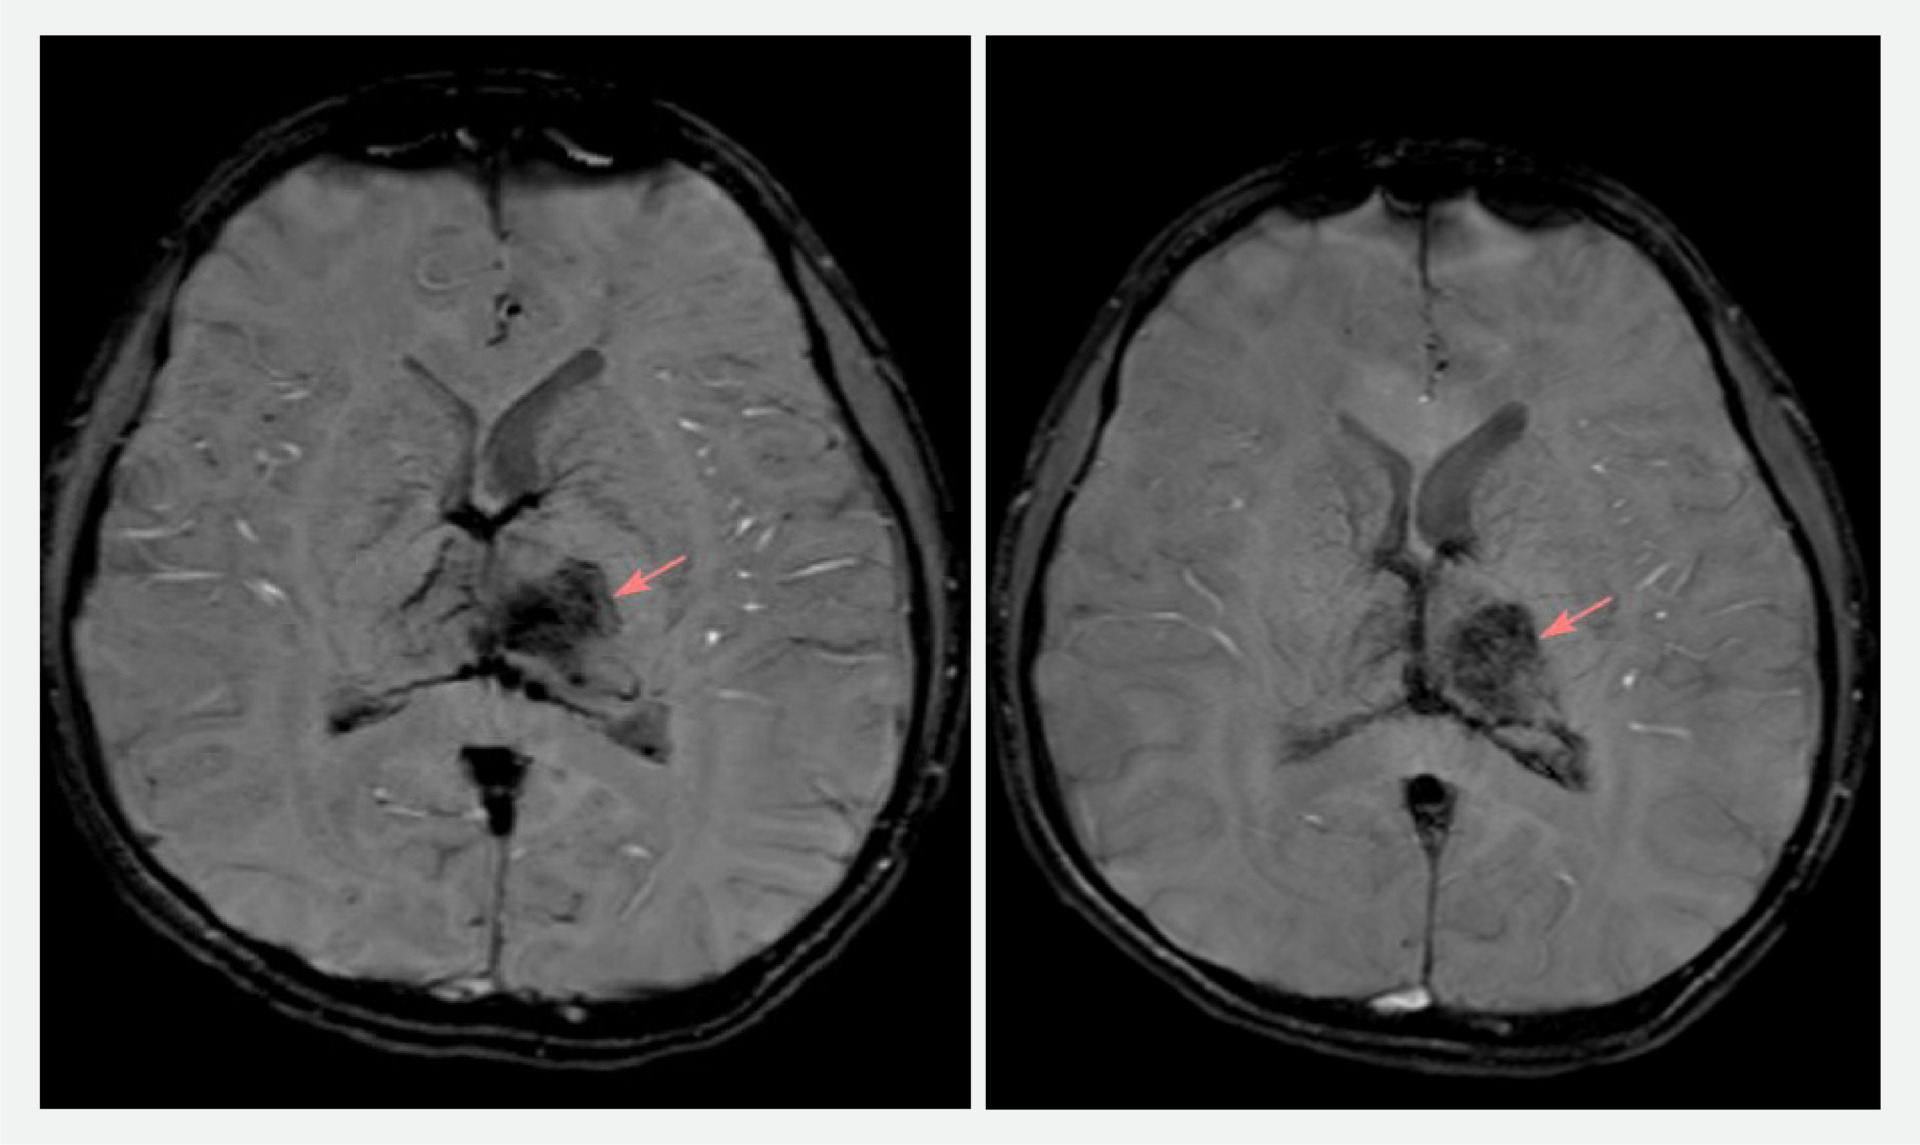

Bệnh nhi được nhân viên y tế và người nhà đưa đến Bệnh viện Đa khoa Quốc tế S.I.S Cần Thơ để tiến hành chụp MRI não. Kết quả ghi nhận tình trạng xuất huyết não, phù não vùng đồi thị.

Các bác sĩ của 2 bệnh viện cùng hội chẩn, đưa ra chẩn đoán xác định là đột quỵ xuất huyết não do tắc tĩnh mạch Galen. Sau đó, em T. được hướng dẫn nhập viện can thiệp điều trị cấp cứu tại Bệnh viện Đa khoa Quốc tế S.I.S Cần Thơ.

Hình ảnh chụp MRI não của bệnh nhi trước và sau khi can thiệp 1 ngày (ẢNh: BVCC)

ThS.BS Lê Minh Thắng – Đơn vị Can thiệp mạch DSA, Bệnh viện Đa khoa Quốc tế S.I.S Cần Thơ – bác sĩ can thiệp trực tiếp cho biết: “Trường hợp của em T. khá hiếm gặp trên thực tế. Dựa trên kết quả chụp MRI ghi nhận tình trạng xuất huyết não kết hợp với phù vùng đồi thị. Các bác sĩ đã tiến hành can thiệp lấy ra rất nhiều cục máu đông trong tĩnh mạch Galen và xoang thẳng, khai thông được tĩnh mạch bị tắc nghẽn”.